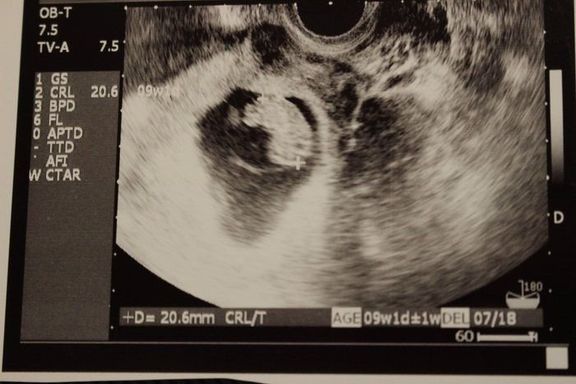

"おなかの中はどうなっていくの? エコー写真で振り返る、高齢ママのはじめての妊娠生活" -

緊急帝王切開で誕生。エコー写真で綴る息子と過ごした252日 -

安静指示に、妊娠高血圧症候群。支えは息子のエコー写真、トラブル続きの妊娠生活 -

不妊治療や2度の流産経験を経て「初めての出産」。日々成長する胎児の記録をエコー画像で振り返る -